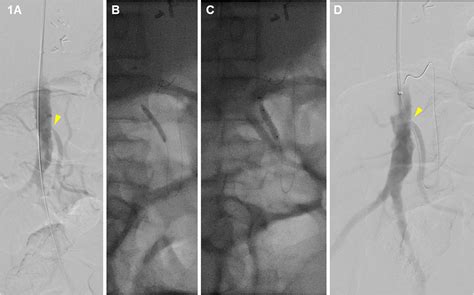

• Angioplasty and Stenting: A minimally invasive procedure where a small balloon is used to open the artery, and a stent is placed to keep it open. This is often the preferred first-line treatment for its shorter recovery time.